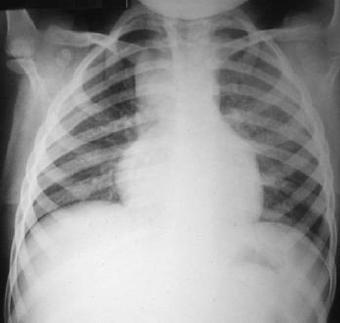

Radiografía del tórax

Rx. Tórax PA. Radio transparencia conservada en ambos campos pulmonares, sin infiltrados parenquimatosos, hileo y patrón de flujo pulmonar normal, senos costo y cardio-diafragmaticos libres, silueta cardiaca posición central normal, puede notarse el ensanchamiento del mediastino, por loe mas prominente en el lado derecho aspecto lobulado bien limitado, el esqueleto y partes blandas sin alteraciones.

Rx. Tórax LI. Radiopacidad peritraqueal redondeada y lobulada prominente en mediastino anterior y superior que incrementa el contraste de radiotrasperencia traqueal, observándose estenosis en su porción distal.